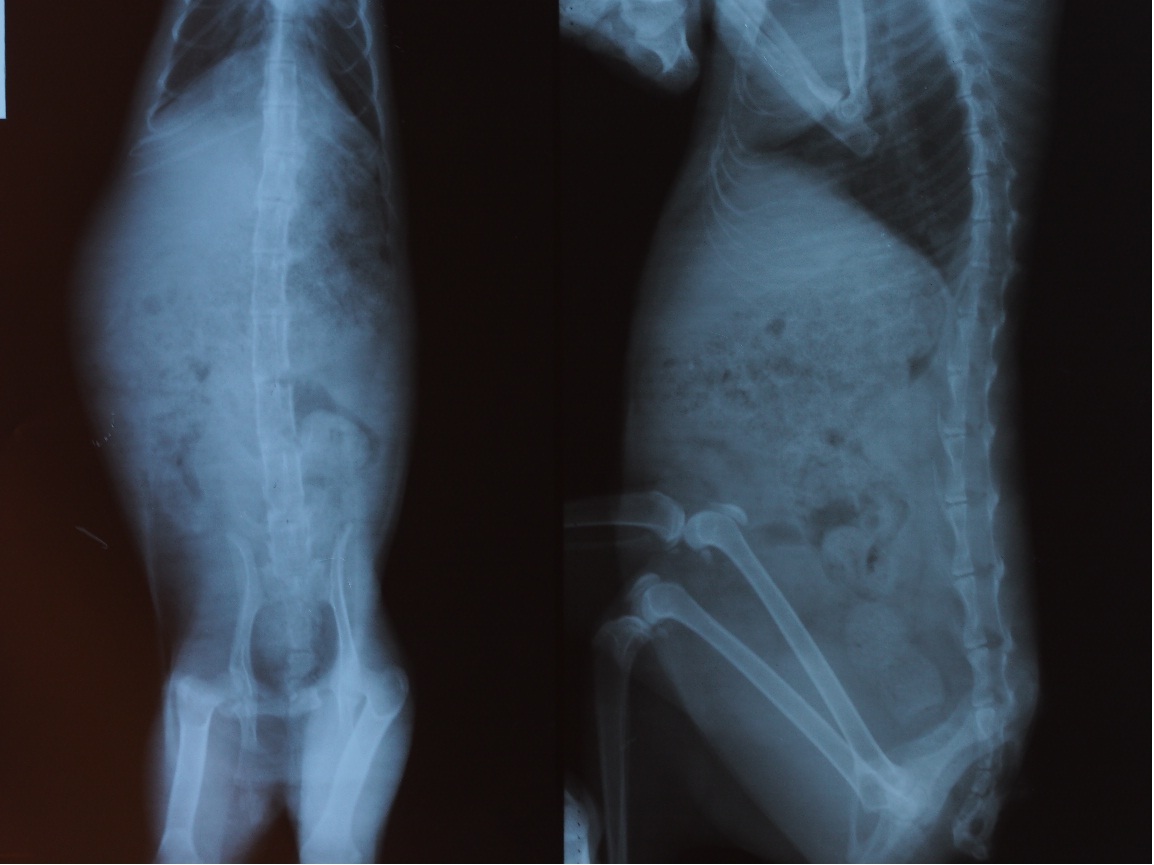

主題: 桃園/平鎮 跛腳貓被狗咬傷 申請者姓名: 高雅慧 花色: 申請日期: 2013-03-25 20:49:57 申請者部落格: 申請者臉書網址: 所在縣市/合作醫院: 桃園縣/思邁爾動物醫院 治療費用: 7240元 需求人數: 16人 已結案 (2013-04-12 10:54:51) 報名人員: PandaLi(已付款)、Ginny Cat(已付款)、Amy(已付款)、Jill Tsou(已付款)、Szu-Yi Lai(已付款)、Martin Chen(已付款)、林廷軒(已付款)、Nico Liu(已付款)、小寶兔(已付款)、Jessica Hsieh(已付款)、許若溱(已付款)、Amy H. T. Lin x2(已付款)、nina(已付款)、陳倩婷(已付款)、小摳咪(已付款)、 候補人員: 月、蕭大萍、 動物病情說明: 小黑貓可能小時候有被車撞過,後骨盆歪掉,走路、跑步都有點障礙,有一天下班在家附近看到他似乎後腳癱掉,背部腐爛,

帶去給醫生看,醫生把毛剃掉以看到肉,有4個大洞,

皮肉都分離,醫生評估應該是被狗咬的,

須開刀將壞死的部分切掉、縫合、觀察,

後腿部分X光照出無太大問題,骨頭與肉已長出,所以不用動手術,

可能是因為太痛動不了,